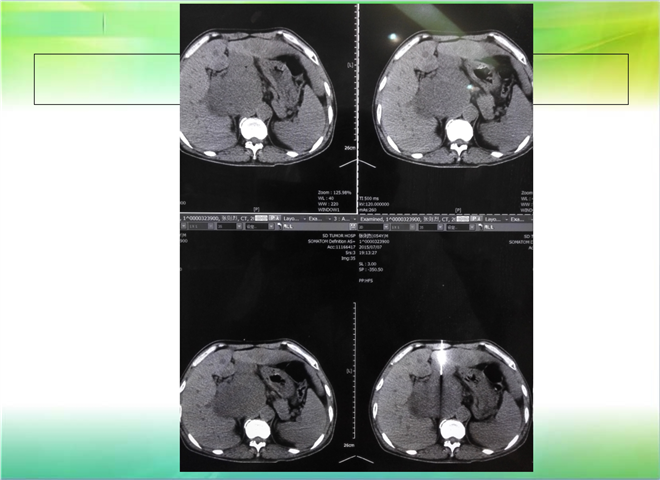

CT引导下穿刺活检术